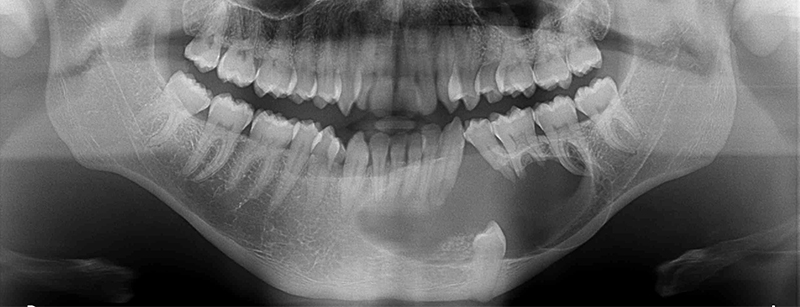

L’examen de la radiographie panoramique montre la présence d’une volumineuse lésion ostéolytique, d’aspect multinucléé, bordée d’un liseré ostéocondensant, localisée au niveau mandibulaire de la 43 à la 36 avec refoulement du germe de la 34 au niveau du rebord basilaire, de résorptions radiculaires au niveau des 33, 35 et 36 et ponctuée de calcifications intralésionnelles.

Fig. 01 : image ostéolytique radioclaire monogéodique de contour net >5cm localisée au niveau de la symphyse et de la branche horizontale mandibulaire gauche. Cette image est parsemée de fines ponctuations radio-opaques en rapport avec la dent incluse n°35 refoulée dans le rebord basilaire et présence de résorptions radiculaires inflammatoires au niveau des dents 43, 34, 36 et 37 en imagerie panoramique.